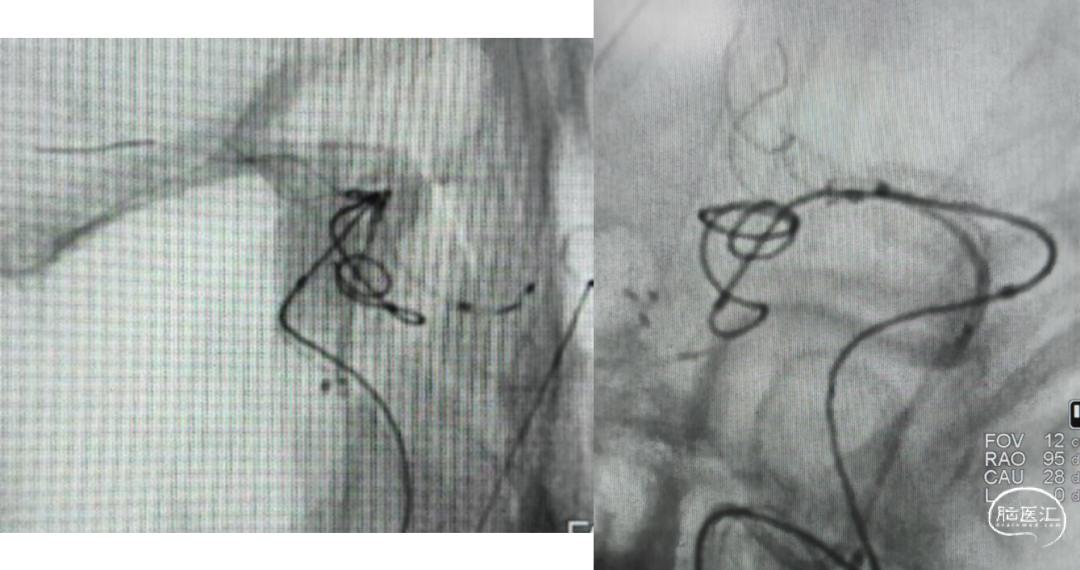

微导管塑形

echelon10(45)J-7(90右偏90)-15(90);echelon10(90)J-5(45右偏90)-15(90)

Axium3d620;axium3d15

管2:target3d24